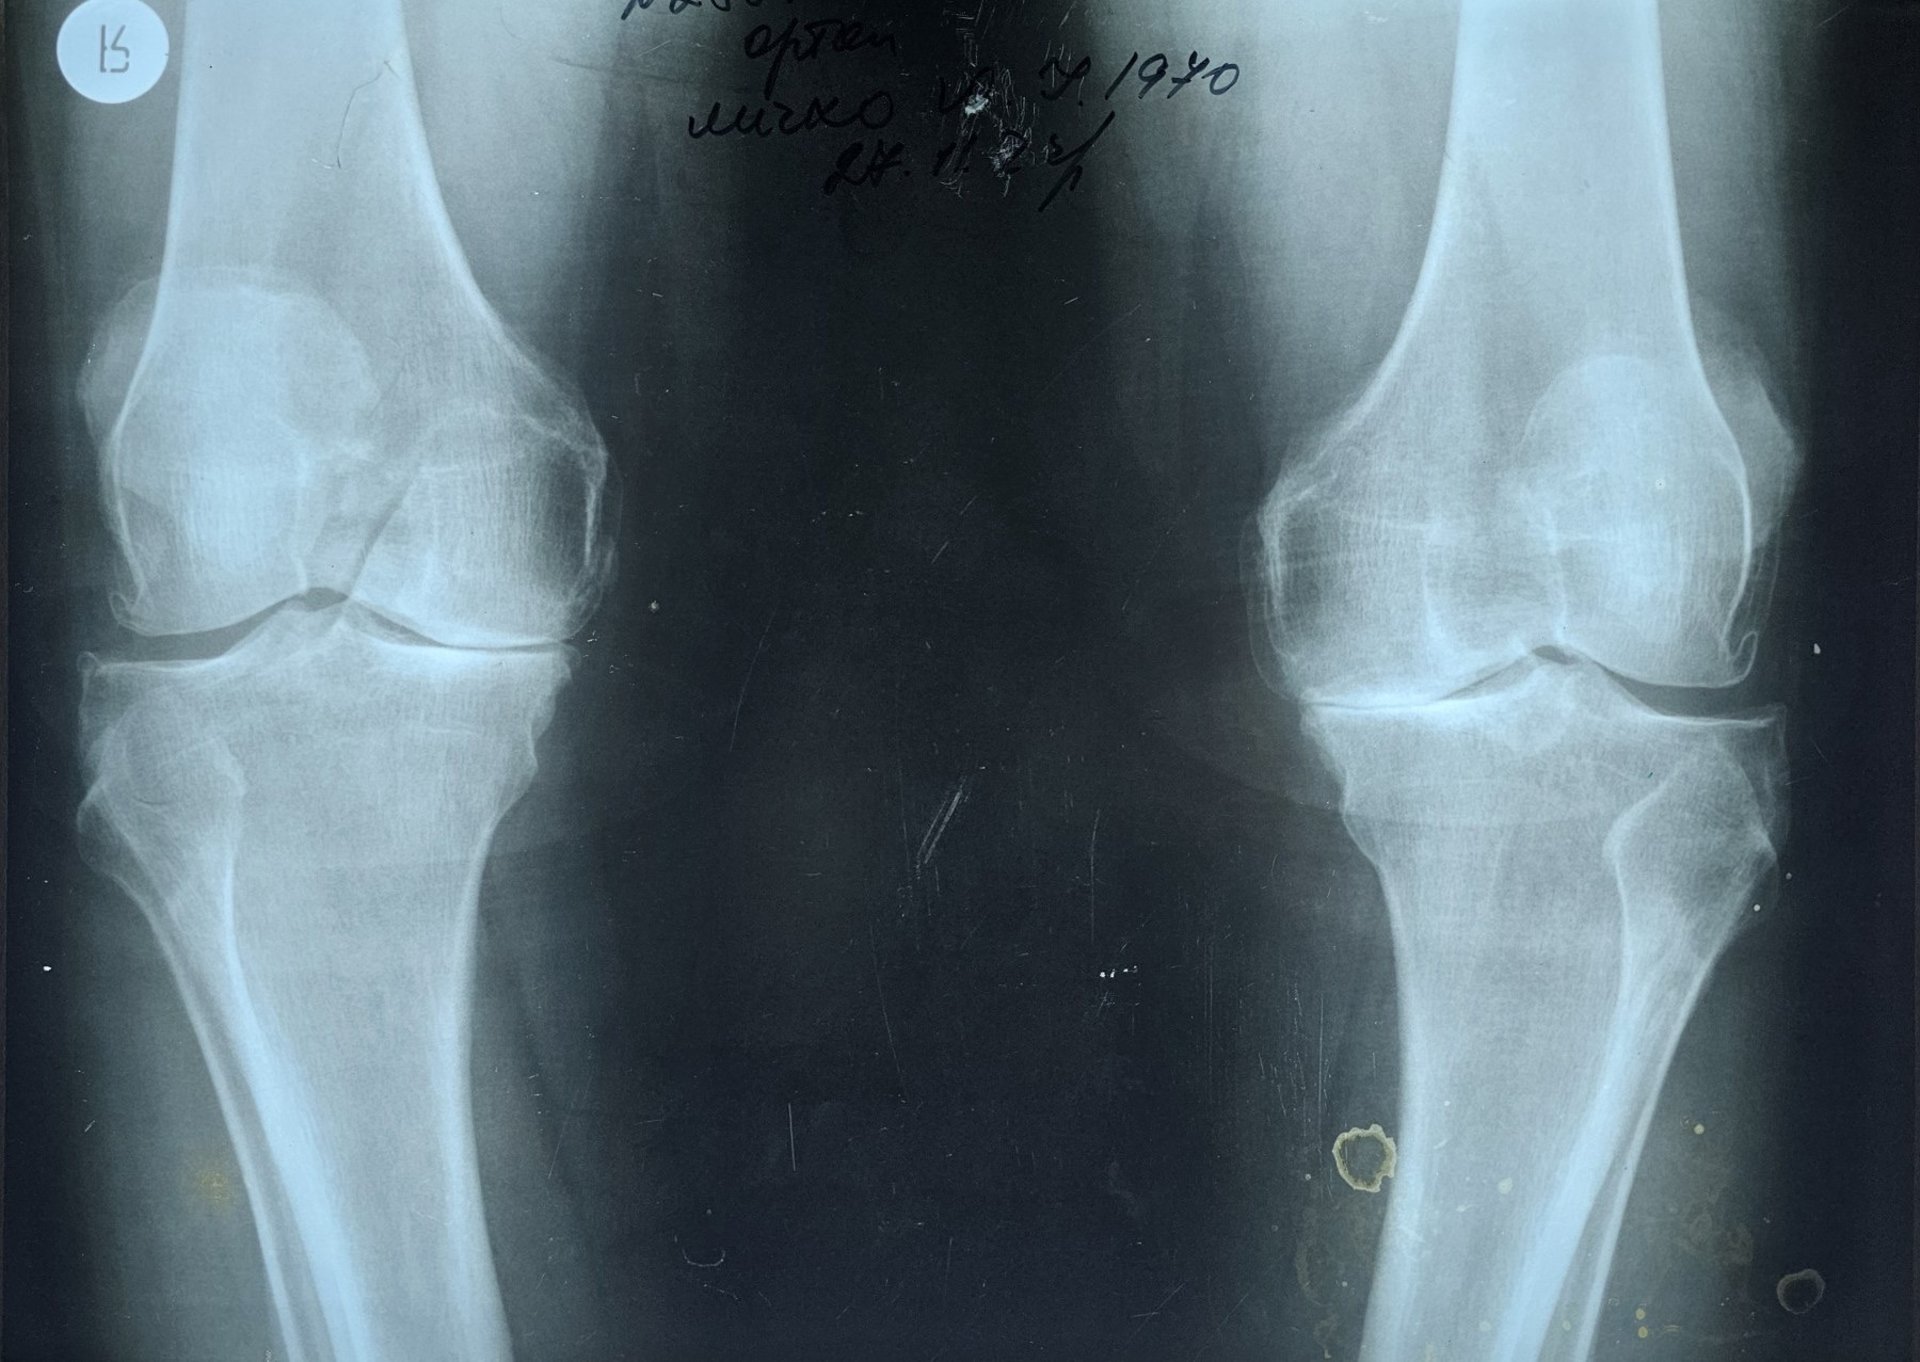

Як розповіли на сторінці медзакладу, пацієнтом став 55-річний Юрій, який від початку повномасштабного вторгнення служить сапером в одному з підрозділів. Через значні фізичні навантаження під час виконання бойових завдань у нього з часом з’явилися сильні болі в обох колінах, деформація суглобів та суттєве обмеження рухливості.

До лікарні чоловіка госпіталізували з діагнозом двобічного гонартрозу IV ступеня з варусною деформацією обох колінних суглобів, стійким больовим синдромом та згинально-розгинальною контрактурою середнього ступеня.